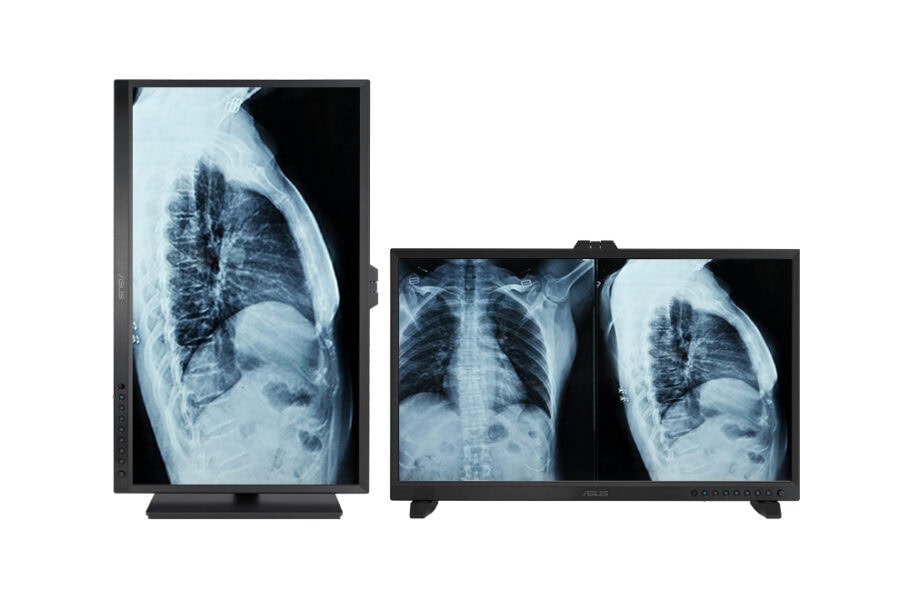

Çok Yönlü Stant

Çok yönlü iki stant seçeneği, HA3281A’yı hastane ortamlarına uygun şekilde yerleştirmenizi kolaylaştırır. Böylece kullanıcılar iş yerlerinde en uygun çalışma veya izleme pozisyonunu bulabilir.

Birlikte verilen ergonomik stand, eğme, döndürme, kendi ekseni etrafında çevirme ve yükseklik ayarlamaları sunar. Ekranı saat yönünde veya saat yönünün tersine 90° dikey yönde döndürebilmek, röntgeni kontrol ederken veya uzun belgelerle çalışırken kullanışlıdır.